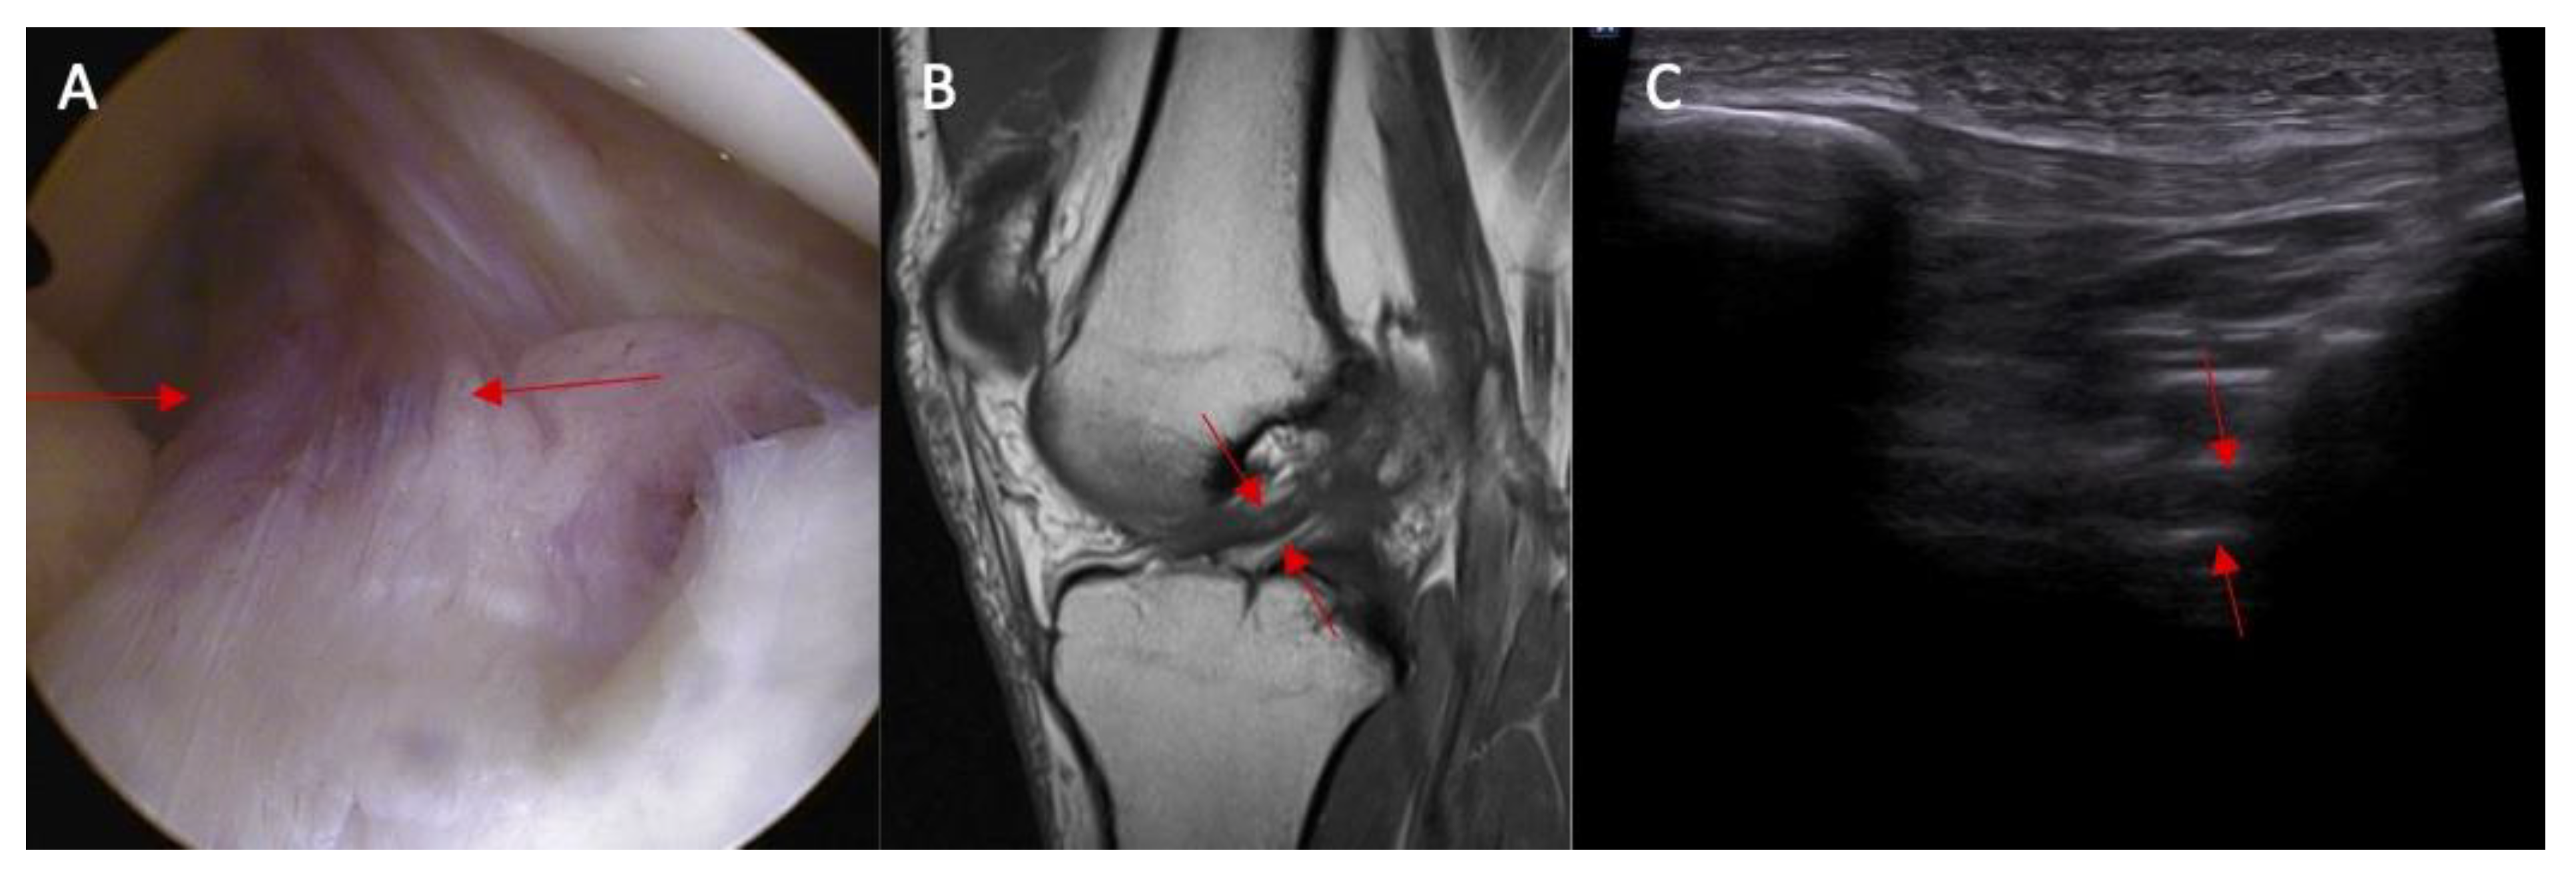

Swelling of the ACL intact to femur condyle was more common in patients with an ACL injury than in those without an ACL injury (83% vs. 0%, respectively, and p < 0.0001) (Figure 5). OR = incalculable.

Figure 5.

The proximal attached (marked with arrows) view of the ACL tear with edema. (A) arthroscopy view; (B) MRI view; and (C) ultrasound view—swelling of the ACL proximal attached to lateral femoral condyle.